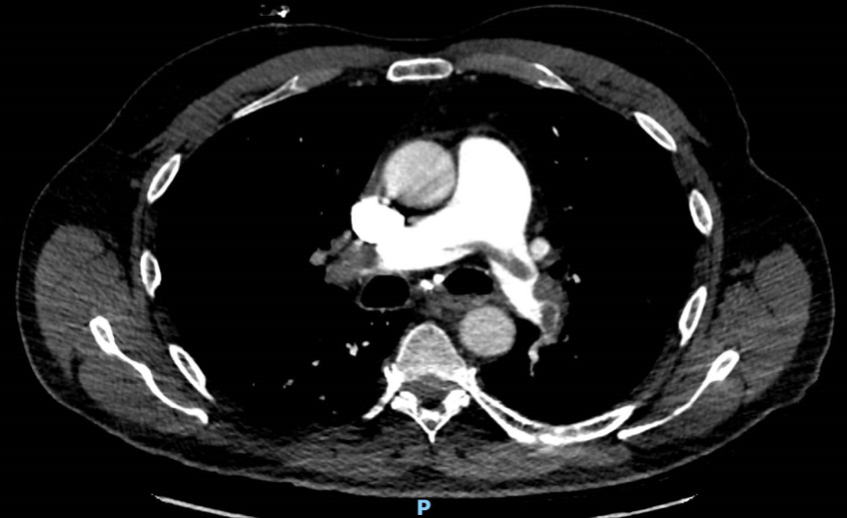

L’échographie cardiaque donnera le diagnostic.

– la tamponnade liquidienne (l’échographie cardiaque donnera le diagnostic) ;

– l’embolie pulmonaire grave (l’échographie cardiaque affinera le diagnostic en cas de dilatation des cavités droites.